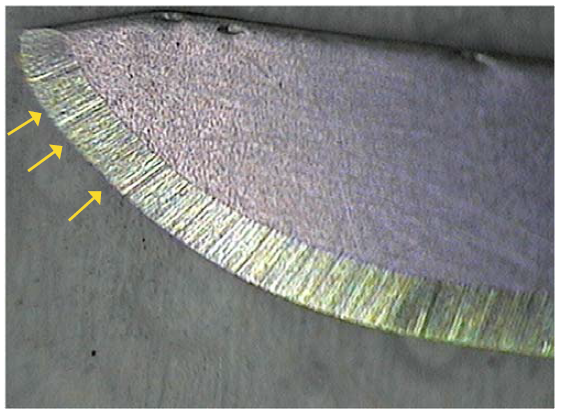

One of the most important evaluated conditions of the study allowed us to determine physical deformation of the scalpel blades from both brands; 75% of the Elite ® blades were deformed regardless of the number of cuts; while deformation percentage of Paramount ® scalpel blades was 90%. This shows the high deformation frequency of scalpel blades after use (Table IV). Nevertheless, in order to obtain better details of the generated deformation degree, scalpel blades areas were analyzed before and after performing the diverse cuts (Figures 3 and 4).

Figure 3 Elite ® D3 scalpel blade before use. Continuity of the sharp edge in the active edge is noticeable, without any opacities or deformities.

Similarly, it is affirmed that after the first cut is performed, deformation of the scalpel blades increases, which can be expressed in qualitative terms; the moment we visually compare photographs from before and after.

After conducting photographic analysis using ImageJ software, where the area of the active part of the blade was measured using photographs from before and after, it is possible to conclude that decrease of scalpel blade's photographed area is directly related to the number of cuts performed with each blade.